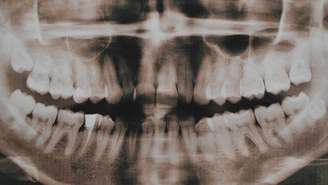

A hiperdontia é uma alteração do desenvolvimento dentário em que surgem dentes extras, os dentes supranumerários – depositphotos.com / YuliyaM

A hiperdontia é uma alteração do desenvolvimento dentário em que surgem dentes extras, os dentes supranumerários. Em vez dos 20 dentes de leite e 32 dentes permanentes normais, algumas pessoas apresentam um ou mais elementos adicionais. Ademais, eles podem nascer na frente da boca, no céu da boca, entre os dentes ou até permanecer totalmente inclusos no osso, sem se tornarem visíveis.

Clinicamente, a hiperdontia pode causar atraso na erupção dos dentes permanentes, desalinhamento, mordida cruzada e, em alguns casos, dor ou inchaço. Quando esses dentes supranumerários permanecem presos dentro do osso, a detecção costuma ocorrer em exames de rotina, como radiografias panorâmicas. Nestes casos, os dentistas as solicitam para acompanhar o crescimento craniofacial, principalmente na infância e adolescência.